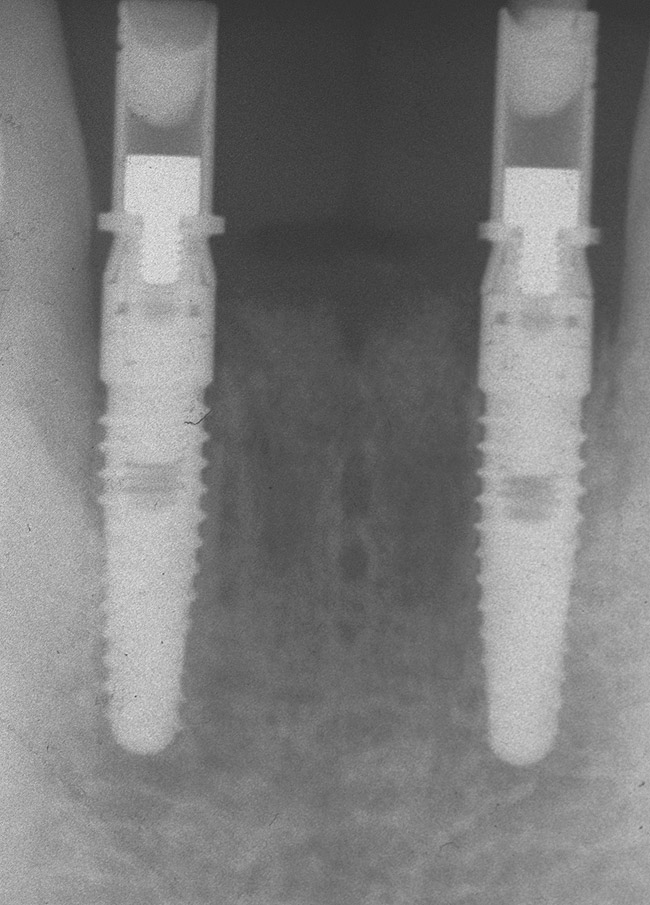

Preoperatively, 1 g of amoxicillin was administered. Using local anesthesia (lidocaine 1:100,000 epinephrine), extractions of teeth No. 23 to No. 26 were performed without raising a flap and with gentle luxation to preserve the remaining facial osseous plate. The sockets were curetted prior to implant placement. A vacuum-formed surgical guide, fabricated based on a diagnostic wax-up of the desired tooth positions for the subsequent fixed prosthesis, was used during implant placement. Osteotomies were performed at sites No. 23 and No. 26 and positioned toward the lingual aspects of the sockets (Figure 3A and Figure 3B). Two tapered implants (OsseoTite™ 313, BIOMET 3i™, Palm Beach Gardens, FL) measuring 3.25 mm x 13 mm were placed. Conical prosthetic abutments (3-mm height) were used to facilitate joining the two implants in a screw-retained fixed partial denture (Figure 4). A laboratory-processed acrylic-resin provisional restoration was altered to allow connection to the temporary cylinders. The provisional was placed into the vacuum-formed surgical guide that was now used to maintain the provisional in the correct 3-dimensional position (Figure 5) while being attached to the temporary cylinders with acrylic resin intraorally. Once a sufficient amount of acrylic resin was placed to secure the cylinders to the provisional, it was removed from the mouth and its contours were completed at the laboratory bench (Figure 6A). The two central incisor sockets were grafted with small-particle allograft material (Puros® Allograft, Zimmer Dental, Carlsbad, CA) to maintain gingival architecture beneath two ovate pontics (Figure 6B). The provisional restoration was inserted and the screws tightened to 20 Nt-cm of torque.

Figure 4  Tapered implants with conical transgingival abutments and temporary cylinders in place.

Figure 4